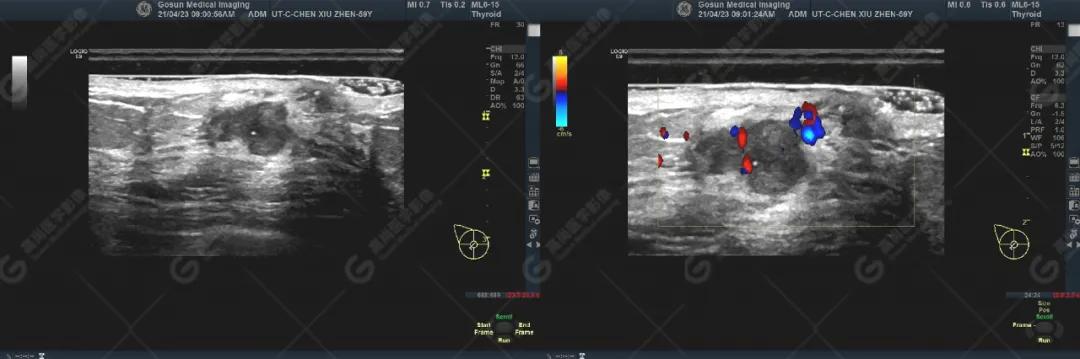

右乳头处见一低回声团块,大小约6mm×7mm,其下方探及一实性低回声团块,大小约17mm×14mm,两者相连,周边与部分导管相连,团块边界欠清,形态不规则,内部可见散在点状强回声,局部见密集点状强回声,CDFI显示周边及内部见丰富血流信号,PW显示较大者Vp=10cm/s,RI=1.0。

超声图像

1) 乳头回声不均匀减低,伴或不伴乳晕区皮肤增厚,增厚乳晕区皮肤与后方脂肪层分界不清。

2) 乳头、乳晕回声异常伴下方大输乳管及远端乳管扩张,管腔内可见低回声,并见多发性微钙化。

3) 乳头、乳晕回声异常病例均能在乳头局部探及丰富血流信号,合并导管内原位癌(ductal carcinoma in situ,DCIS)/非特殊型浸润性癌时可见肿块,肿块形态多不规则,边缘模糊不清,内部呈不均质低回声。肿块内均能探及走行杂乱、扭曲、管径粗细不均匀血管。